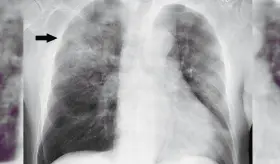

Algunos virus, pulmonía, asma y otras condiciones comparten síntomas y hasta hallazgos radiológicos, por lo que solo un especialista puede diferenciarlas con precisión.